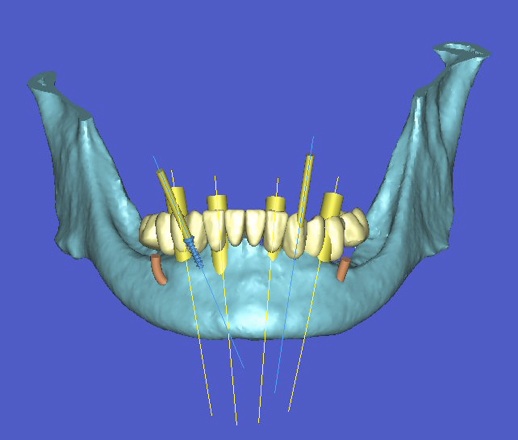

l’informatique au service de l’implantologie

La société Materialise a développé un logiciel SIMPLANT qui permet de simuler la position des futurs implants et de les transférer en bouche à l’aide d’un guide chirurgical.